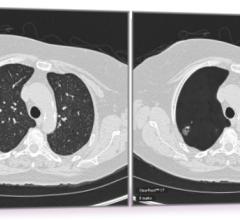

Riverain Technologies announced that the United States Patent and Trademark Office (USPTO) has awarded the company a broad patent for its artificial intelligence (AI) computed tomography (CT) technology. The technology in question forms a vessel suppressed, chest CT series using deep learning and synthetic data modeling. The company said the patent holds promise for improving the detection and diagnosis of lung cancer at an earlier stage while making clinicians more efficient, a first for computer-aided detection (CAD).